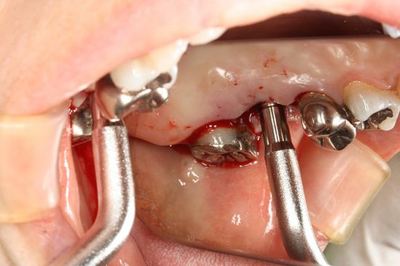

切開線を入れて粘膜剥離をして深さを正確に確認します。

ストローマンインプラント純正のボーンコンデンセーションとオステオトームで

ソケットリフトを行います。